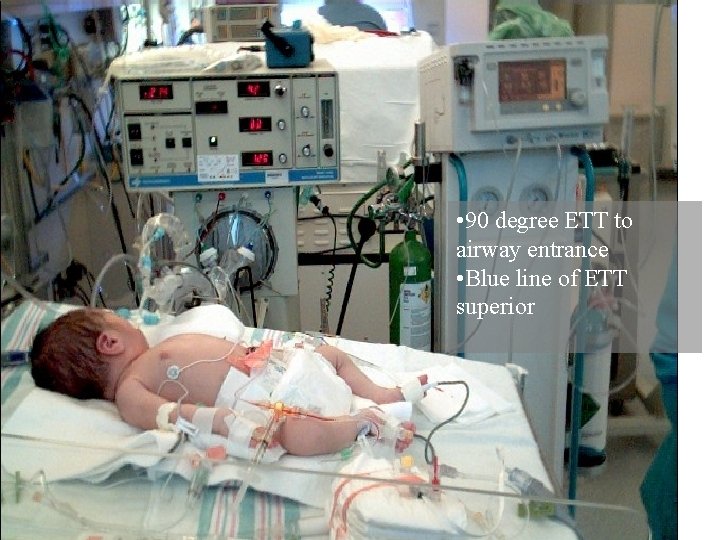

• 90 degree ETT to airway entrance • Blue line of ETT superior